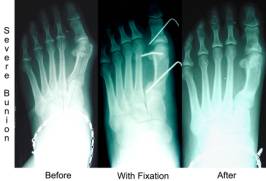

If your IM angle is over 14 degrees we call this a severe bunion. This usually requires work to be done at the base of the metatarsal. We can reduce the IM angle to almost zero depending on the structure of the rest of the forefoot.This requires you not to walk on the foot for a period of 6-7 weeks. A combination of procedures may be necessary with severe bunions. We may need to do work at the head of the bunion also.